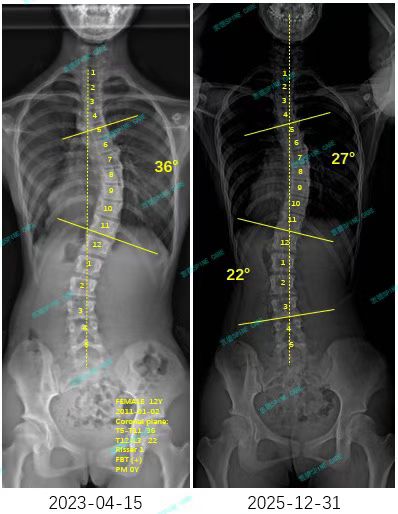

来自家长对衷德的评价(言言妈妈)

衷德脊柱,我们只关注侧弯保守治疗~